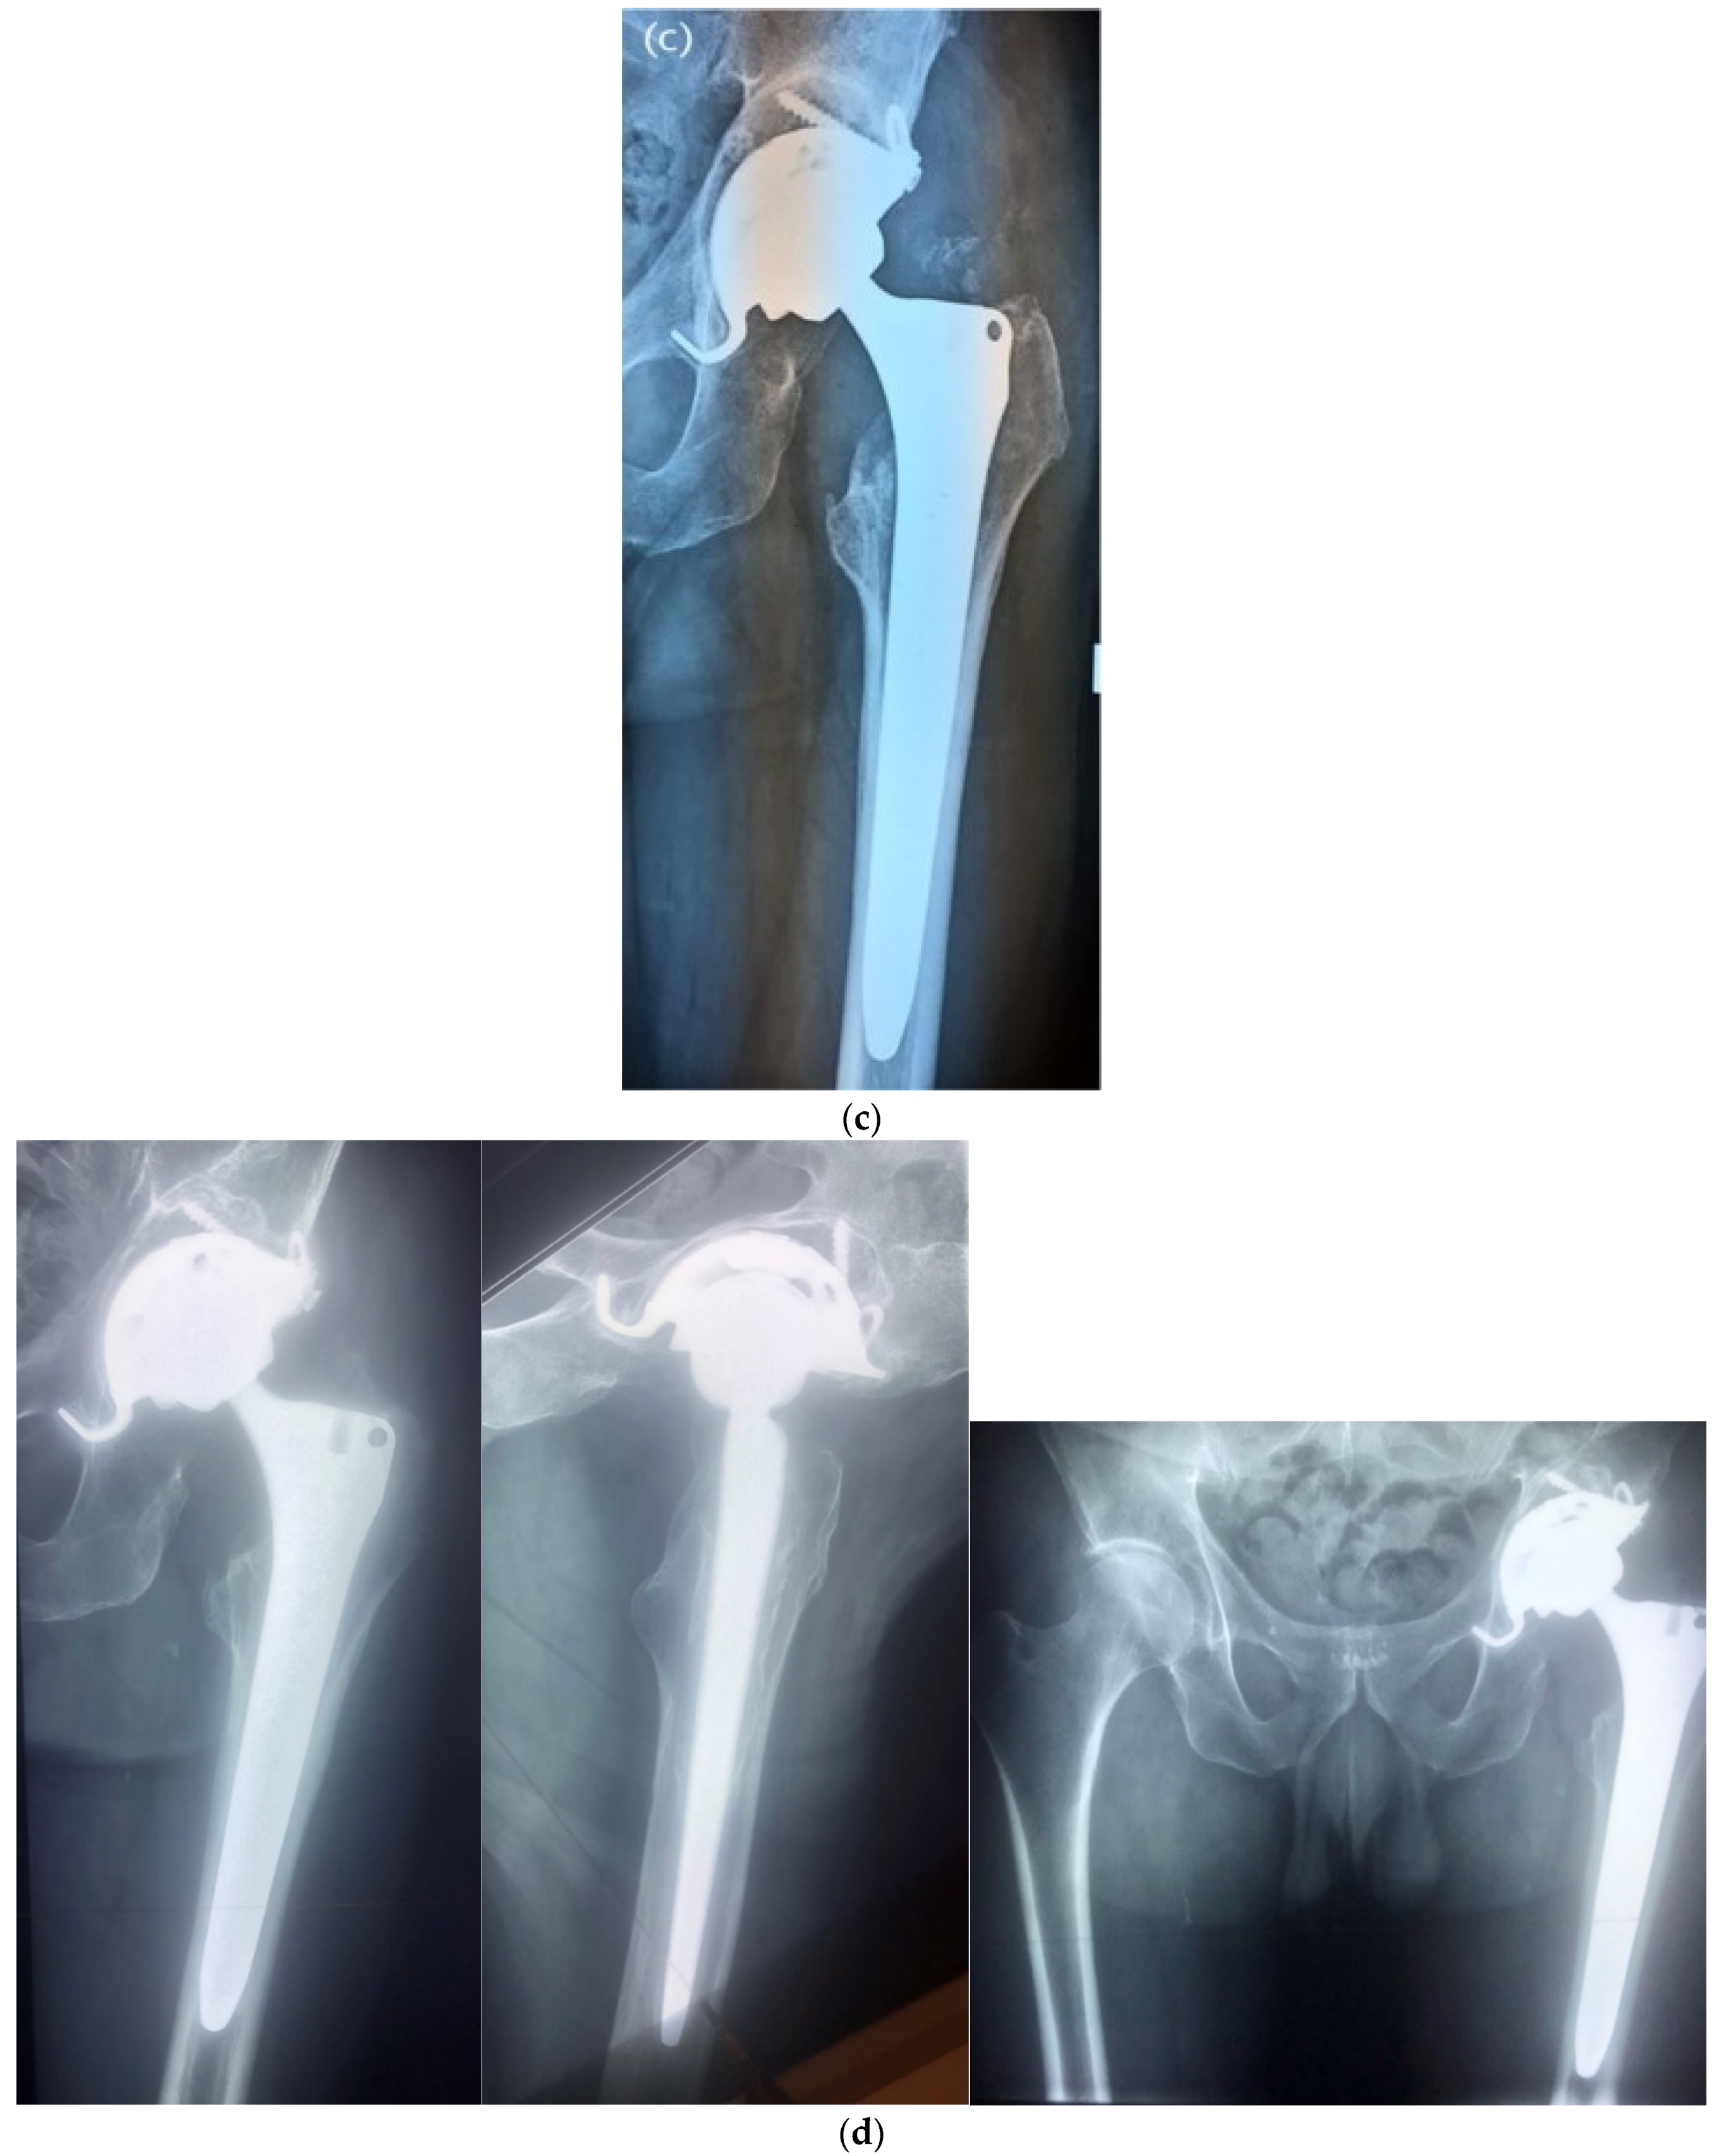

| Hip Joint | 38 (54.3%) |

| Volume antibiotic-impregnated allograft bone (cm3) | 92.2 ± 27.8 (40–202) |

| Cementless prosthesis implantation | 49 (70%) |